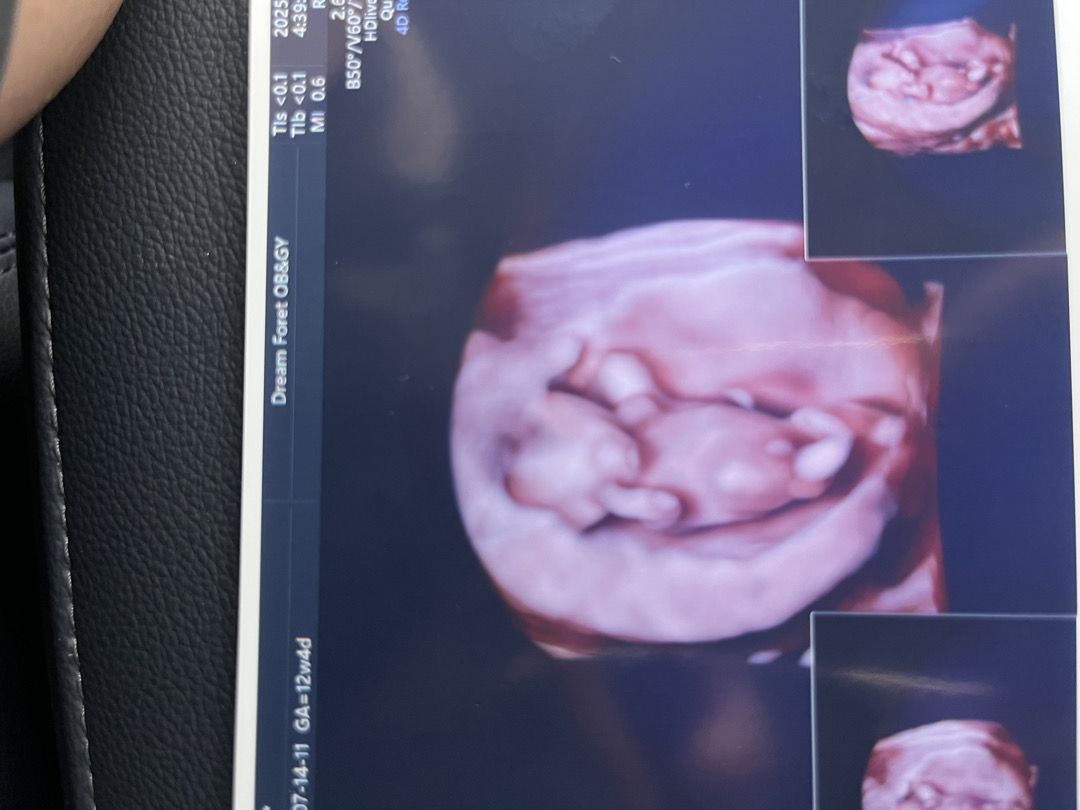

12주 4일차 정밀초음파 보고왔는데 남자아인가요? 배꼽일까요?

보이는대로 보는게 맞을까요? ㅎㅎㅎ

탯줄 같아요